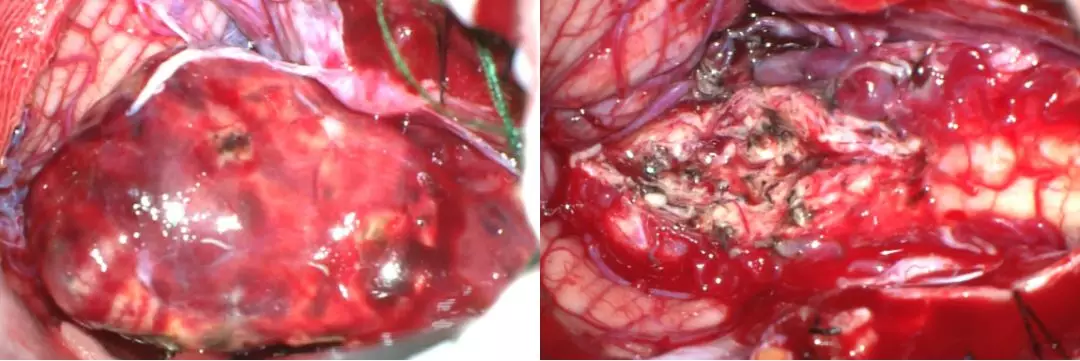

手术过程

然后取俯卧位,头架固定,导航注册定位,常规消毒铺巾,先穿刺右侧枕角,留置脑室外引流一根。接着做枕下后正中入路开颅,切开皮肤,分离肌肉,暴露枕骨麟部,枕下骨窗成型,咬开C1后弓。

Y字形剪开硬膜,翻向上方及两侧,打开枕骨大孔处蛛网膜,即可暴露肿瘤。吸除栓塞后的少量血肿,并从下方抬起病灶,小心逐根电凝离断病灶供血动脉,一一剪断。避开引流静脉,分别从右侧,上方及左侧反复电凝并离断病灶供血动脉。病灶张力逐渐下降,引流静脉颜色变暗。

肿瘤深部累及四脑室底部及延髓,予以小心保护。最终离断引流静脉后,将病灶完整切除。进一步探查迂曲的引流静脉,未见明显出血。术野严格止血后关颅,硬膜修补缝合,骨瓣还纳,逐层缝合肌肉及皮肤。术中出血约500ml。